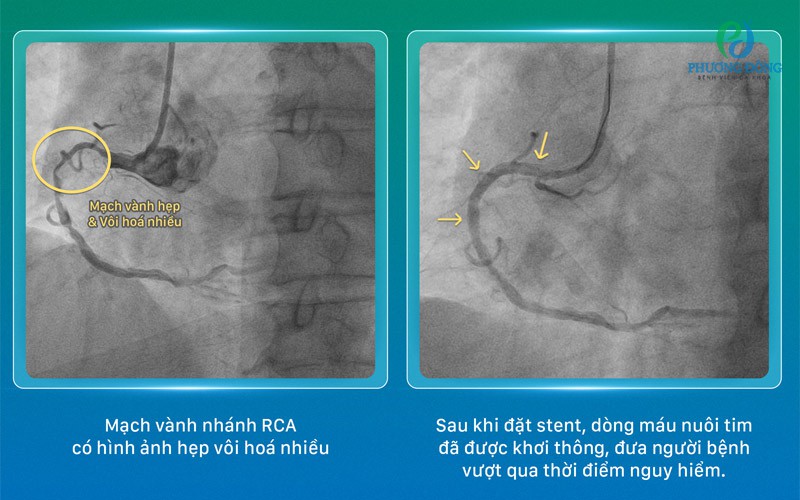

Bệnh nhân nhập viện trong tình trạng đau ngực trái kéo dài kèm theo các triệu chứng chóng mặt và đau đầu dữ dội. Qua kết quả chụp mạch vành tại bệnh viện, các bác sĩ xác định hệ thống cấp máu cho cơ tim của người bệnh đang ở mức báo động đỏ. Tình trạng hẹp khít xảy ra đồng thời ở cả ba nhánh mạch vành chính với tỷ lệ tắc nghẽn lần lượt là 91% tại nhánh RCA, 95% tại nhánh LAD và 87% tại nhánh LCx.

Ca bệnh này được đánh giá là một thách thức lớn đối với đội ngũ y bác sĩ khi đồng thời tồn tại nhiều yếu tố nguy cơ cao. Hệ mạch máu của bệnh nhân không chỉ bị hẹp mà còn bị tổn thương bởi tình trạng xơ vữa lan tỏa, vôi hóa nặng và cấu trúc mạch xoắn phức tạp, gây trở ngại lớn cho việc đưa thiết bị can thiệp vào lòng mạch.

Dưới sự dẫn dắt trực tiếp của TS.BS Tạ Tiến Phước, ê-kíp chuyên gia đã xây dựng một kế hoạch can thiệp tổng thể vô cùng chi tiết. Quá trình thực hiện đòi hỏi sự chính xác tuyệt đối trong việc lựa chọn thứ tự xử lý từng nhánh mạch, đồng thời kiểm soát nghiêm ngặt áp lực khi nong bóng và đặt stent. Mọi diễn biến trong lòng mạch đều được đánh giá liên tục để điều chỉnh kỹ thuật theo thời gian thực.

Sự hỗ trợ của hệ thống chụp mạch số hóa xóa nền (DSA) đóng vai trò then chốt, giúp các bác sĩ định vị chính xác vị trí tổn thương và kiểm soát từng cử động nhỏ của thiết bị với độ an toàn tối đa. Sau những giây phút tập trung cao độ, ca can thiệp đã thành công rực rỡ, dòng máu nuôi tim được tái lập hoàn toàn, giúp bệnh nhân vượt qua giai đoạn nguy kịch và ổn định sức khỏe nhanh chóng.